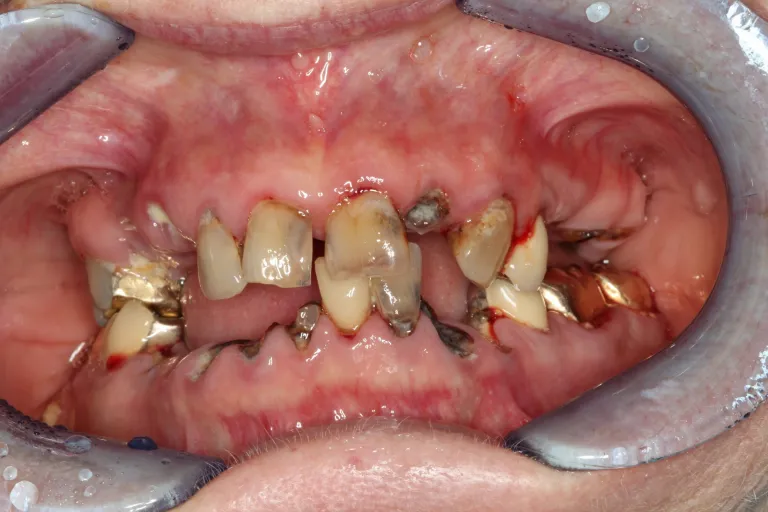

“Beyond Repair: Transformative Bone Grafting and Implant Therapy for Devastating Anterior Teeth Loss”